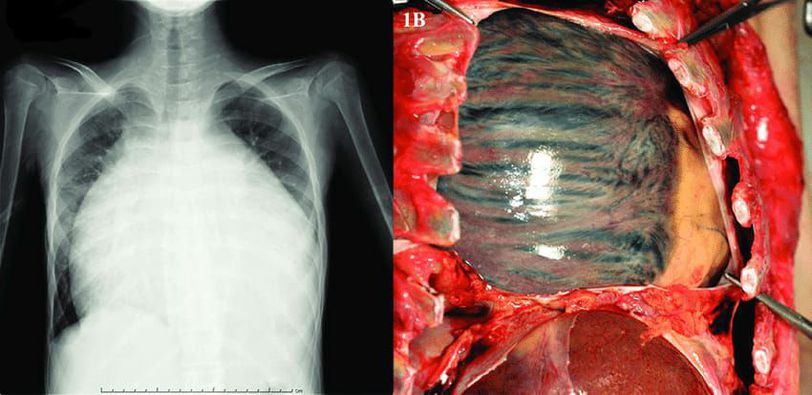

EXTREMELY ENLARGED HEART⚠️

Cardiology

Heart

Enlarged